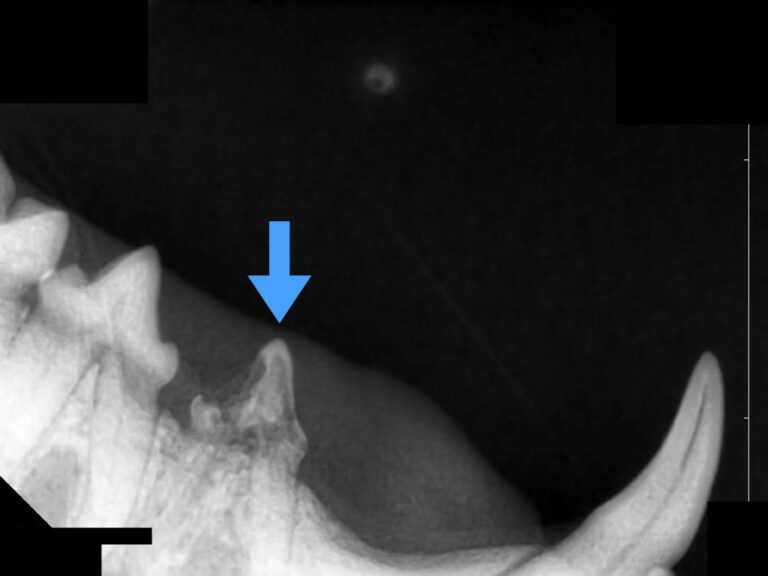

下の写真を見てみましょう。

下顎の第一後臼歯に歯石が沈着し、歯肉が後退しているのが分かります。

沈着している歯石を除去すると、歯根が見えるほど歯槽骨が融解していることが分かりました。

歯科レントゲンを撮ってみると歯を支える歯槽骨が重度に融解しており、重度歯周病と診断しました。

そのため、この歯は抜歯をせざるを得ない状況でしたが、抜歯処置も非常に困難な処置となりました。

この症例はあまりにも歯槽骨の融解がひどく、抜歯時に下顎骨を骨折してしまうリスクがありました。

また、この大臼歯の真下には太い血管が走行しているため、歯を抜く際に血管を傷つけると大出血してしまうリスクもあります。

幸いこの症例は骨折も大きな出血もなく無事に抜歯処置を終えましたが、歯周病を放置すると歯を抜かなければいけないだけでなく処置自体のリスクも高くなってしまいます。